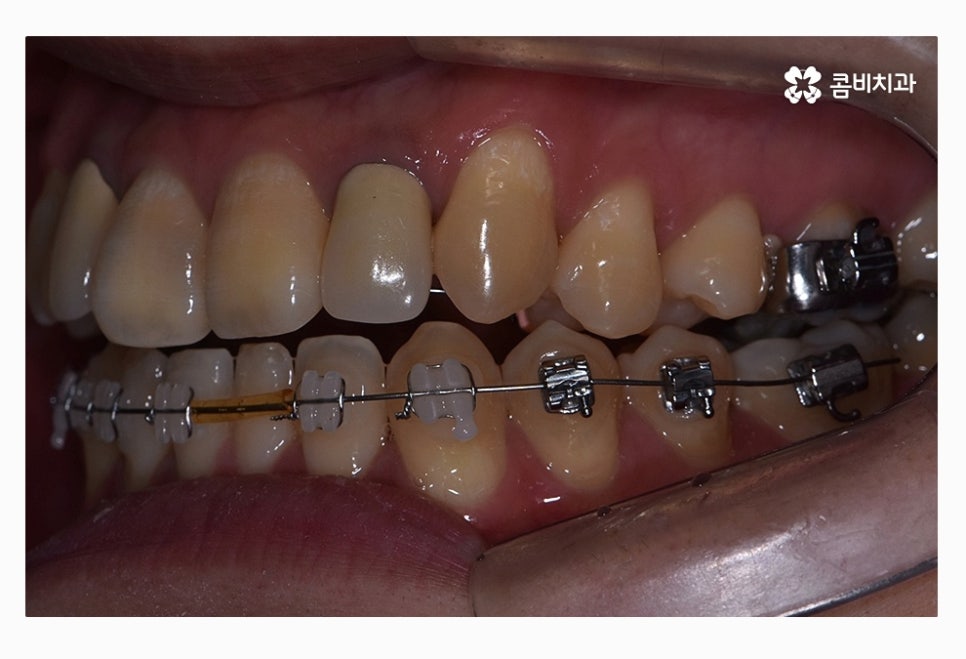

위 환자분의 경우 치열을 볼 때 정면에 비해서 측면으로 보면

앞니가 삐뚤어져 있는 것이 눈에 띄며 교합이 맞지 않아

윗니가 아랫니를 정상적으로 덮지 못하고 있는 상태이며

치아의 이동 공간 및 교합 등으로 볼 때 비발치로

치료가 가능했던 사례라고 할 수 있어요.

위 사진은 교정 장치를 부착한 초기 사진이며

아래는 콤비교정 진행하고 약 1년 정도 지난 후 사진이라고 할 수 있는데요.

윗니에서 앞니가 유독 삐뚤어져 있던 상황이었는데

반듯하게 자리를 잡아가고 있으며 아랫니에서도

삐뚠 부분이 있었는데 가지런하게 자리를 잡아가고 있어요.